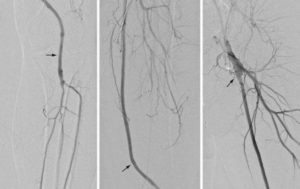

- Ангиографию – рентгеноконтрастное исследование, позволяющее определить на рентгеновском снимке место сужения или закупорки сосуда.

- Ангиография – проводится оценка характера сужения вены и обнаруживается закупоренный участок по ходу сосуда.